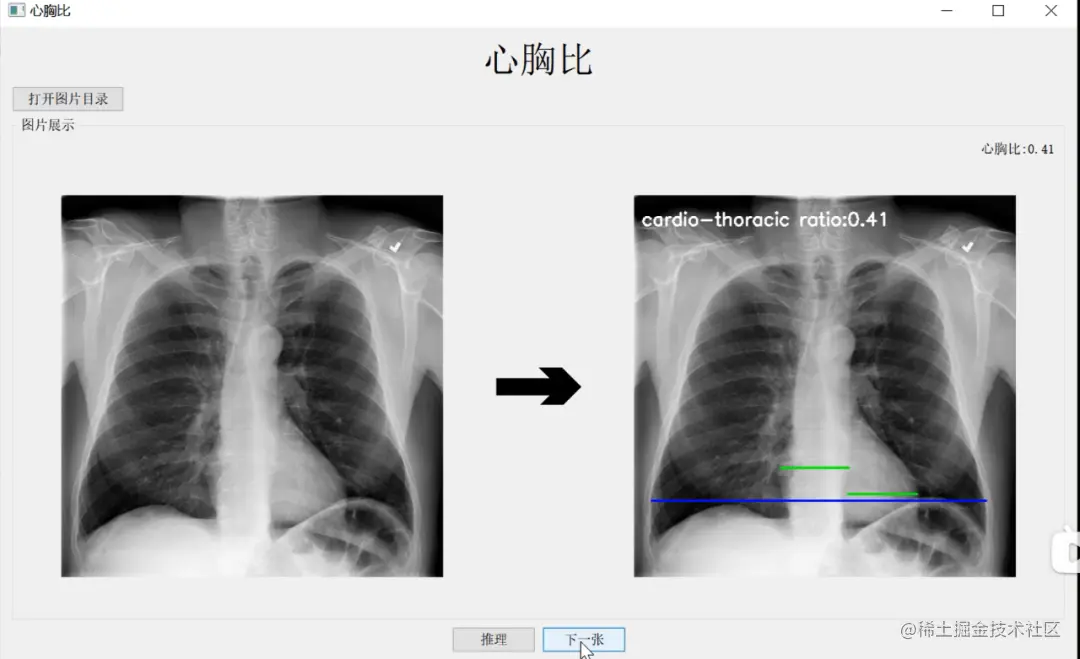

他重点介绍了“快速测心胸比”项目。放射科医生在下诊断之前,会花费不少时间看医学影像图像,测量各种数据指标,从而更好地判断患者的病情。测心胸比是影像诊断中判断心脏是否增大的常用手段,心胸比是指在X线片上心脏横径与胸廓横径之比,一般成年人正常心胸比不大于0.5,如果心胸比大于0.5,说明心脏有增大的倾向,患者需要去做进一步的CT检查,确定导致心脏增大的原因。

医师手动计算心胸比需要先测量心脏最大横径

与肺部最大横径,再计算两者比率通常,医院的放射医师手动测心胸比,一天可能要测四五百张,非常耗费时间。此外,由于人的肺部是一个不规则的生理结构,不是简单找到点到点的直径距离就能测出来。因而,人工测心胸比主观性强,容易有误差,可能不同的医生检测出来的结果也并不一样。

冯嘉骏选择使用PaddleSeg 2.0开发工具,实现自动准确测量心胸比,最终使得肺部和心脏的医疗图像分割精度结果分别达到了0.978和0.955的准确率。

作为计算机视觉领域重要的技术之一,图像分割将图像分成若干具有相似性质的区域,是图像语义理解的关键环节。冯嘉骏采取区域分割方法,基于飞桨图像分割套件PaddleSeg,借助其高精度和轻量级优势,将心脏和肺部两个器官的横径准确测量出来,目前该技术已经应用到农田分割、工业机器目标检测、医疗影像分割等领域。